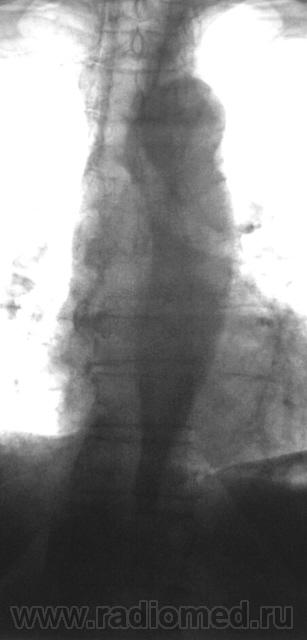

СТРАННО, но кажется, что с аортой всё в порядке - игра теней! Подмигиваю(можно взять на скопию!Молчу-молчу!...)

Аорта, только аорта!

Похоже на "заползшее" лправое легочное поле.) а так конечно стеноз, без супрастенотического расширения ))

Можно предположить, коарктацию брюшного отдела аорты в сочетании с её атеросклерозом II стадии, но я бы для уточнения взял пациента на  R-скопию лёгких.

Добрый вечер. Так интенсивно может выглядеть кальцинированная аорта. Есь стеноз , супрастенотическое расширение и ... аневризма...- я бы сразу назначил РКТ

Добрый вечер, Валентин Львович! Мне кажется - это все-таки игра теней. Переднее или заднее пролабирование правого легкого создает картину изменения аорты. А клинические изменения имеют место?